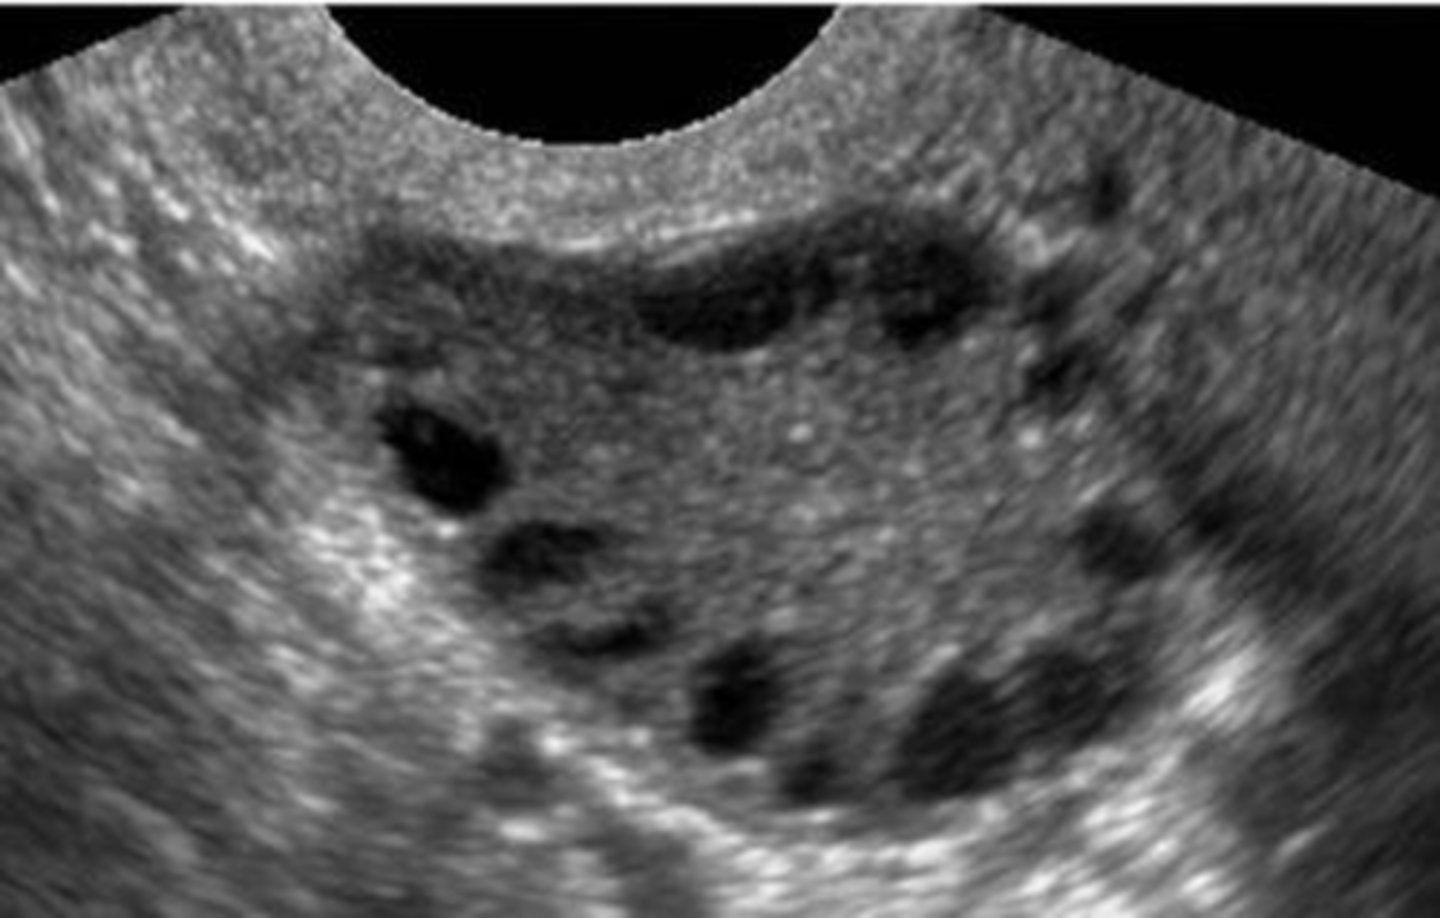

In polycystic ovarian syndrome (PCOS) ___ do not develop normally preventing normal ___

follicles; ovulation

How does PCOS appear sonographically?

normal ovary with multiple small immature follicles; "string of pearls"

What are symptoms of PCOS?

1. oligomenorrhea

2. hirsutism

3. obesity